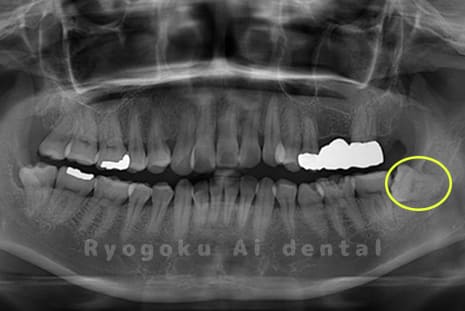

Case04

-

- 原因

- 上顎の親知らず、下顎の水平埋伏の親知らず

- 治療内容

- 上顎の親知らず、下顎の水平埋伏の親知らずを抜歯したケースです。

<リスク・副作用>

手術後は痛み、腫れ、痺れなどの副作用が生じる場合があります。